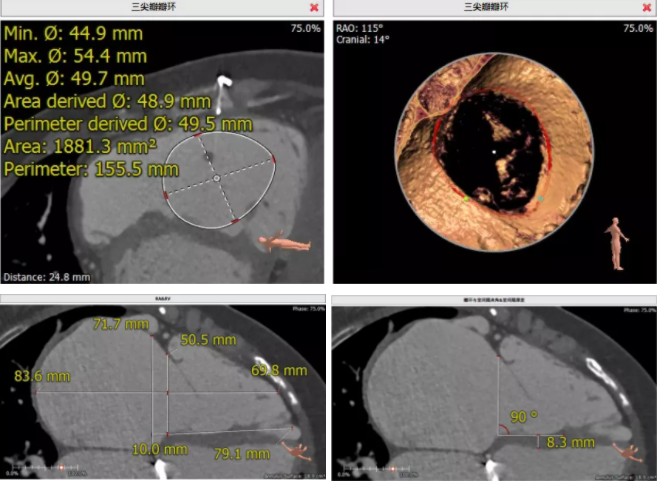

患者為68歲女性,14年前因“反復感冒、氣促”,檢查發現心臟瓣膜病,接受了“二尖瓣機械瓣置換術”。約5年前出現雙下肢水腫,活動后心累氣緊,心臟彩超提示:三尖瓣返流。近年來三尖瓣返流逐漸加重并伴有輕微黃疸、雙下肢水腫,雖長期服用利尿劑治療,但效果欠佳。郭惠明教授團隊結合病史、超聲及CT評估,考慮患者瓣膜置換術后,三尖瓣重度返流,再次開胸行體外循環手術風險高,經團隊整體評估,決定采用最適合患者的LuX-Valve三尖瓣置換系統行微創治療,根據測量結果選擇植入JS/TTVI-28-55型號的LuX-Valve瓣膜。

手術過程